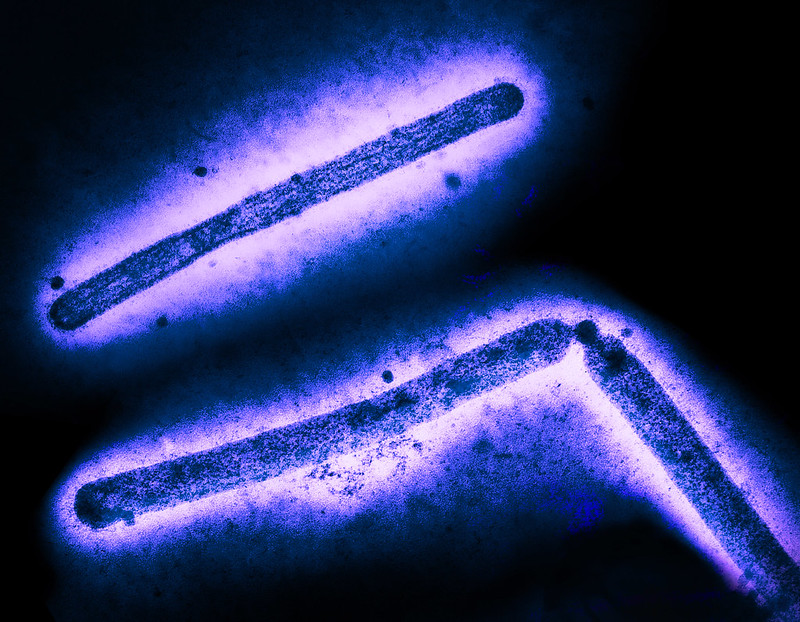

The first case of a person to contract bird flu after no known contact with animals is raising questions about the possibility of human-to-human transmission and highlighting the complicated relationship between states and federal agencies in outbreak response.

An extensive investigation into the case of a patient in Missouri who was hospitalized on 22 August has revealed no links to animals, officials at the US Centers for Disease Control and Prevention (CDC) told reporters on Thursday.